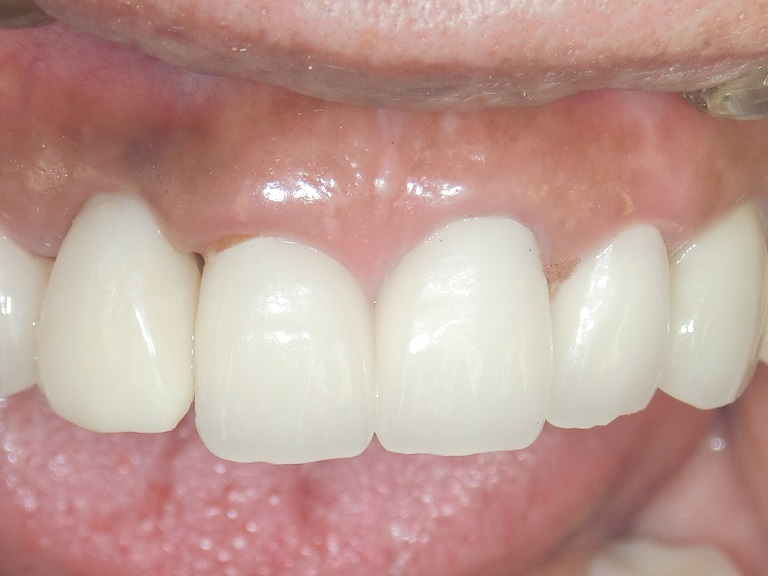

上2番目の歯をインプラント治療をしています(左から2本目) まだプロビジョナル(仮歯)です 最近プラスチックサージェリーという言葉を聞きませんか? 歯肉美容整形オペという意味です もともとプラスチックとは偽物とか仮のとかいう意味であまりよい意味では使いません。 われわれがおこなっているオース…